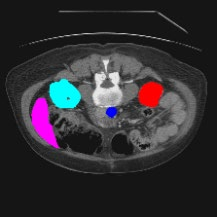

Transformers have made remarkable progress towards modeling long-range dependencies within the medical image analysis domain. However, current transformer-based models suffer from several disadvantages: (1) existing methods fail to capture the important features of the images due to the naive tokenization scheme; (2) the models suffer from information loss because they only consider single-scale feature representations; and (3) the segmentation label maps generated by the models are not accurate enough without considering rich semantic contexts and anatomical textures. In this work, we present CASTformer, a novel type of generative adversarial transformers, for 2D medical image segmentation. First, we take advantage of the pyramid structure to construct multi-scale representations and handle multi-scale variations. We then design a novel class-aware transformer module to better learn the discriminative regions of objects with semantic structures. Lastly, we utilize an adversarial training strategy that boosts segmentation accuracy and correspondingly allows a transformer-based discriminator to capture high-level semantically correlated contents and low-level anatomical features. Our experiments demonstrate that CASTformer dramatically outperforms previous state-of-the-art transformer-based approaches on three benchmarks, obtaining 2.54%-5.88% absolute improvements in Dice over previous models. Further qualitative experiments provide a more detailed picture of the model's inner workings, shed light on the challenges in improved transparency, and demonstrate that transfer learning can greatly improve performance and reduce the size of medical image datasets in training, making CASTformer a strong starting point for downstream medical image analysis tasks.